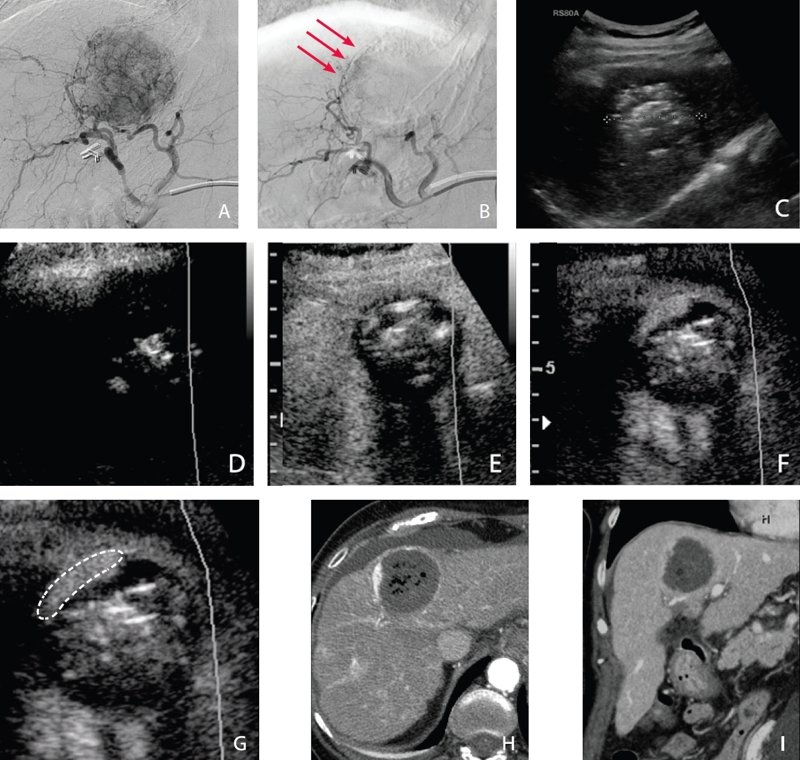

Рис. 3. Ангиографическая демонстрация васкуляризации новообразования (А). Контрольное исследование после селективной эмболизации (В): сохранение минимальных размеров опухоли, которая получает питание благодаря кровоснабжению из правой печеночной артерии (красные стрелки). Ниже - контрольное УЗИ, выполненное на следующий день: в В-режиме (С) можно видеть гиперэхогенное узловое образование, в связи с наличием воздушных участков.

На эхограмме с контрастированием (D), по сравнению с В-режимом, образование выглядит по большей части аваскулярным, что подтверждает данные ангиографии о сохранении активной опухолевой ткани на периферии (F, G). Подтверждение - на изображениях, полученных при МСКТ с контрастированием в артериальную (Н) и венозную (I) фазу. Диагностические признаки соответствуют состоянию после субтотальной терапии печеночно-клеточного рака.